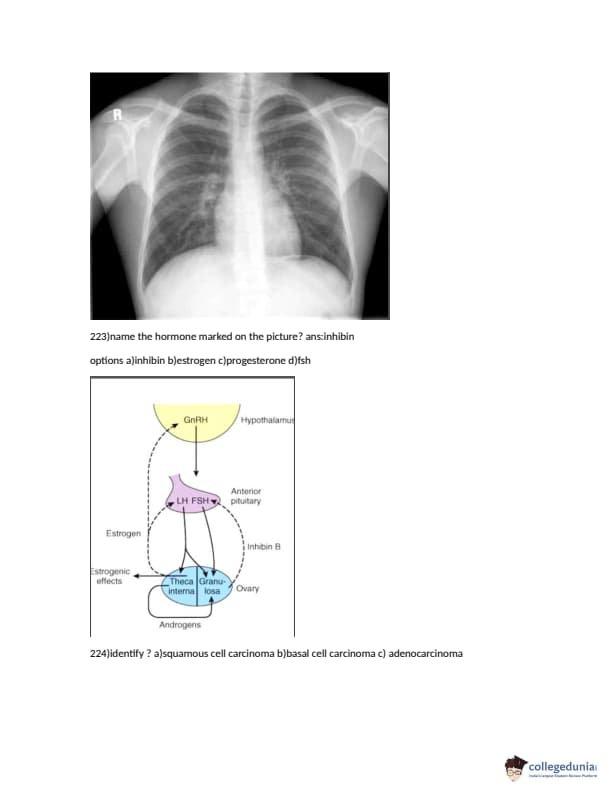

FMGE 2018 Question paper with answer key pdf conducted on December 14, 2018 is available for download. The exam was successfully organized by National Board of Examinations (NBE). The question paper comprised a total of 226 questions.